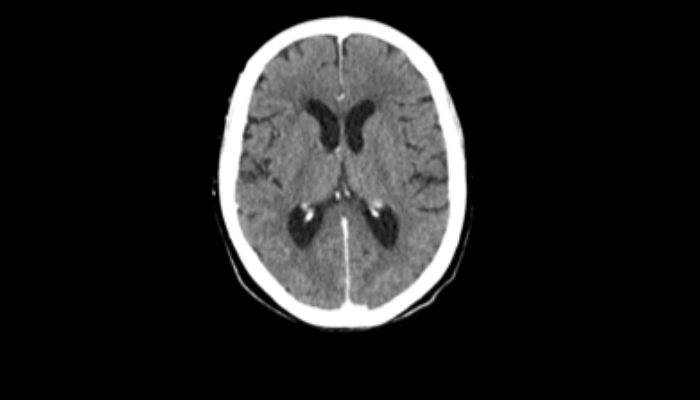

頭部CT画像 頭部CT脳出血や脳挫傷などの評価を行います。 胸部CT画像 胸部CT肺がんや肺炎や大動脈など胸部臓器を評価します。 心臓CT画像 心臓CT冠動脈を評価し、狭心症や心筋梗塞のリスクを検索します。 腹部CT画像 腹部CT肝臓・胆のう・膵臓・腎臓など腹部の重要臓器を評価します。 骨・関節CT画像 関節・骨CT骨折の評価に優れます。 動静脈CT画像 動脈・静脈CT動脈瘤や閉塞性動脈硬化症、深部静脈血栓症など血管の評価を行います。 大腸CT 大腸CT仮想内視鏡と言われる大腸の3D画像を得ることで苦痛の少ない大腸検査をすることができます。検査前日より検査食と下剤を服用していただきます。